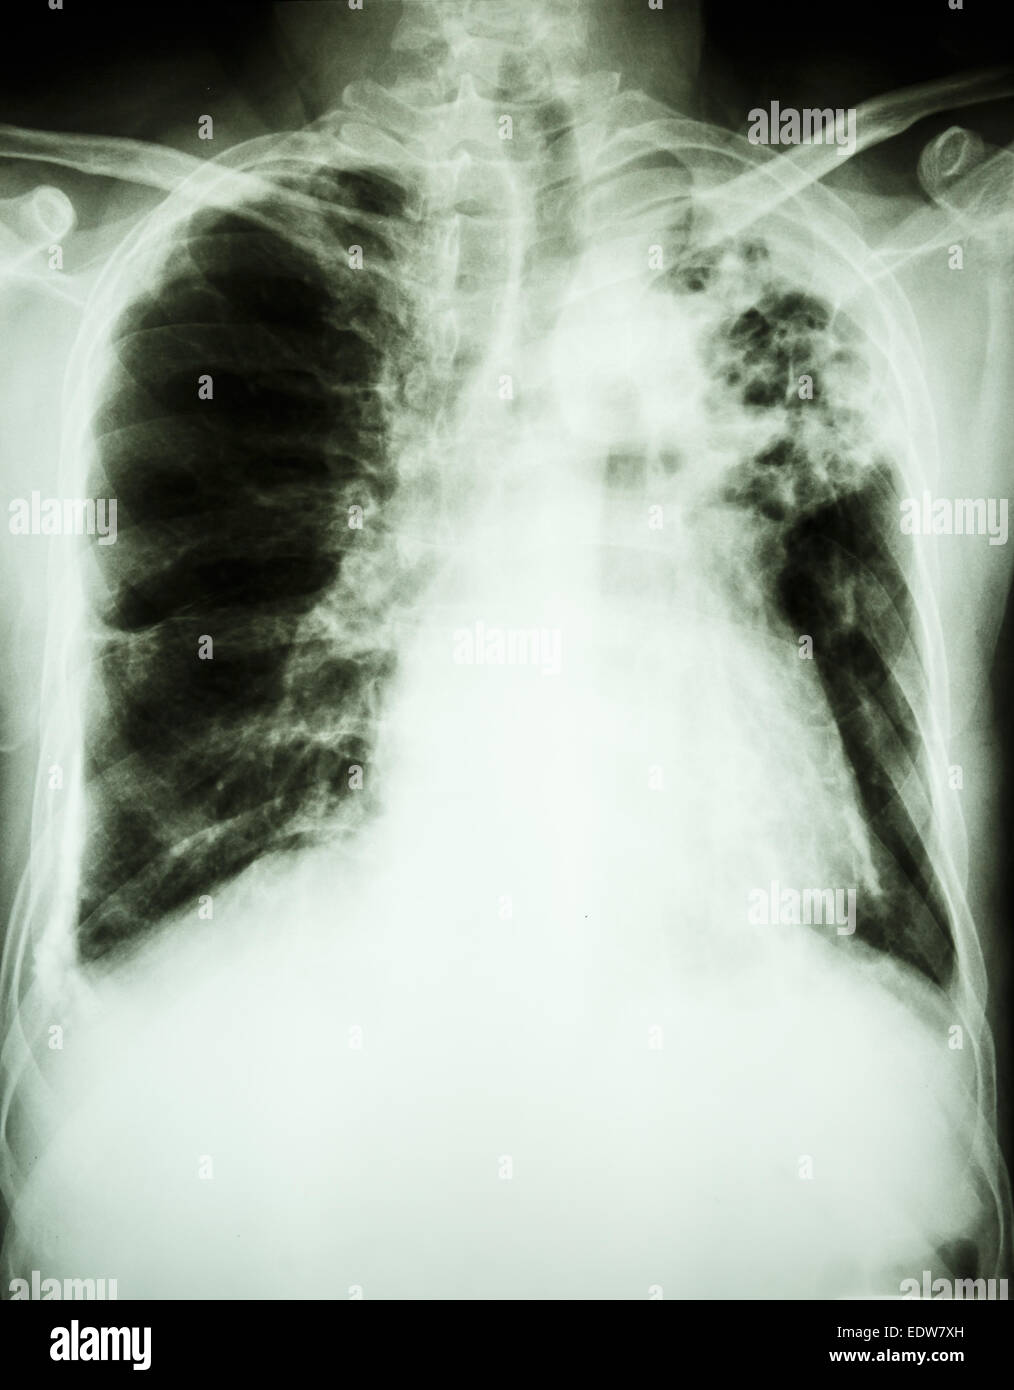

From www.alamy.com

Film Xray show patchy infiltrate at left upper lung from Mycobacterium What Is An Lung Infiltrate Unusual substances in your lungs are known as lung infiltrates, or pulmonary infiltrates. Persistent pulmonary infiltrate results when a substance denser than air (e.g., pus, edema, blood, surfactant, protein, or cells). A pulmonary infiltrate is a substance denser than air, such as pus, blood, or protein, which lingers within the parenchyma of the lungs. Lung infiltrates can show up during. What Is An Lung Infiltrate.